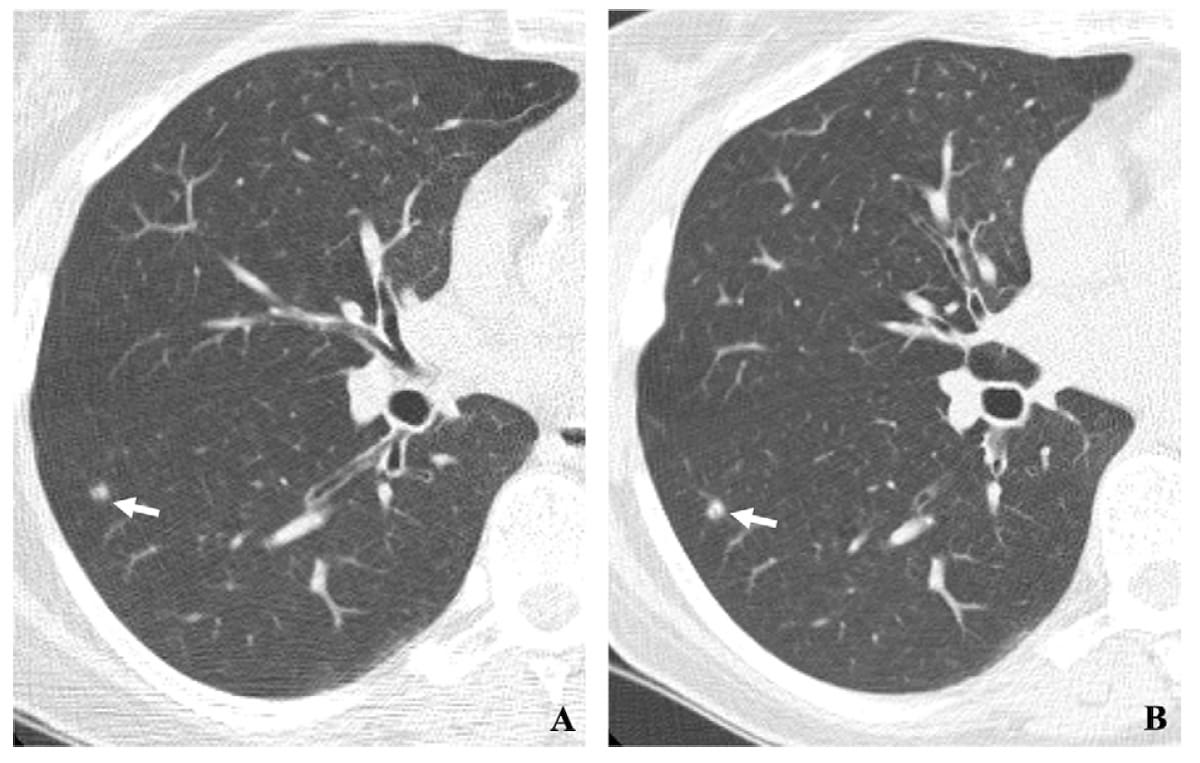

In a multicenter cohort of patients with interstitial lung disease (ILD), a deep learning classification tool demonstrated an 81 percent sensitivity rate and a 77 percent specificity rate for predicting usual interstitial pneumonia on computed tomography (CT) scans.